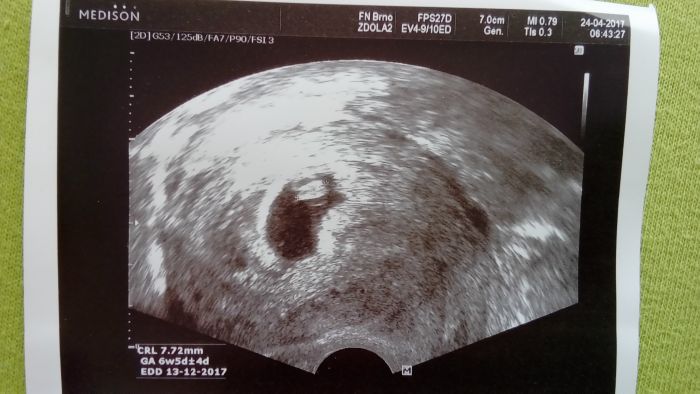

Ještě posílám foto z dneška to bílé místo nad tím plodem je ta krevní srazenina, jinak dneska jsem podle kalkulačky 7+3 a podle ultrazvuku 6+5 tak se mi posouvá termín postupně :D no uvidím na tom velkém ultrazvuku kdy bude tedy termín pokud tedy do té doby bude vše ok jdu za měsíc na další kontrolu a pak po té kontrole se během 14 dní udělá ten velký screening